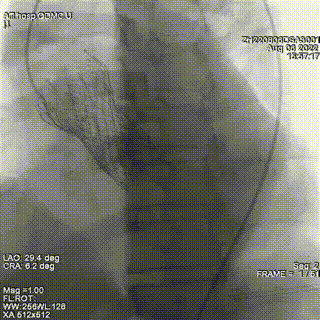

结合术前CTA评估,在S曲线中确定左冠切线位投照角度为LAO32 CRA6, 并在此角度下通过DSA引导导丝通过PVL。